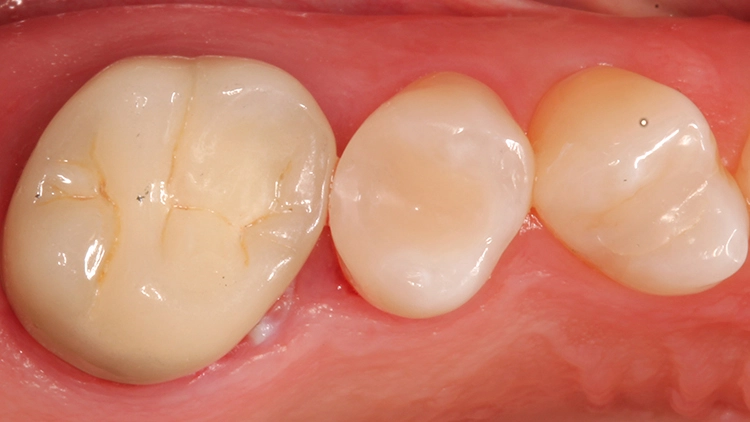

Die Abbildung 6 zeigt die fertig ausgearbeitete (H390Q und 48LQHartmetallfinierer, Komet, Lemgo) und polierte (Diacomp plus Twist DT-DCP10m und DT-DCP10f, EVE Ernst Vetter GmbH, Keltern) Restauration, die sich ästhetisch perfekt in die umgebende Zahnhartsubstanz einfügt. Die Approximalkontakte sind straff, die anatomische Form des Zahnes ist korrekt und die Patientin ist mit dem schnellen Versorgungsergebnis nach 45 Minuten sehr zufrieden.

Der 55-jährige Patient störte sich an dem Randausbruch seines erst 10 Jahre alten Keramikinlays an Zahn 45 (Abb. 7). Er wünschte eine Neuversorgung mit Keramik. Nach eingehender Aufklärung und Beratung konnte er davon überzeugt werden, dass in der Dimension der Kavität eine direkte Kompositversorgung genauso funktionieren könnte.

Der sehr anspruchsvolle Patient haderte zunächst wegen der Ästhetik von „Kunststofffüllungen“: Er war der Überzeugung, dass hier keine adäquate Farbanpassung möglich sei, ließ sich aber auf den Vorschlag der direkten Kompositversorgung ein. Dieser Fall sollte dann eine Challenge für die Universalfarbe Venus Diamond One werden – aufgrund vorangegangener guter Erfahrungen von über 1,5 Jahren mit dem Material [10] konnte man sich ziemlich sicher sein, dass hier automatisch eine adäquate Farbanpassung stattfinden wird und gar keine hochspezifische individuelle Zahnfarbbestimmung erforderlich ist.

Die weitere Versorgung der Kavität erfolgte analog zu Fall 1 nach Anwendung eines klassischen Etch&Rinse-Mehrflaschenadhäsivs und schichtweiser Applikation und Polymerisation von Venus Diamond ONE (Kulzer) mit einem Hochleistungs-LED-Polymerisationsgerät > 1.000 mW/cm2 für jeweils 20 Sekunden Lediglich anstelle des Venus Diamond Flow Baseliners kam aufgrund der sehr hohen ästhetischen Ansprüche des Patienten Venus Diamond Flow in der Farbe A2 zum Einsatz – der Patient hätte keinen weiß-opaken Rand an seiner Restauration akzeptiert. Das Ergebnis (Abb. 9) überzeugte den Patienten nicht nur funktionell, sondern vorrangig ästhetisch: Auch hier passt sich die Universalfarbe perfekt an die Zahnhartsubstanz an. Zur Überprüfung der Ausdehnung der Überkappung wurde im Anschluss an die Versorgung eine Zahnfilm-Röntgenaufnahme erstellt (Abb. 10).